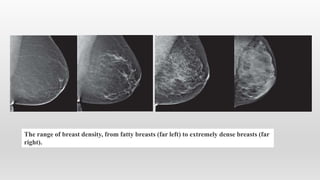

The range of breast density, from fatty breasts (far left) to extremely dense breasts (far

right).